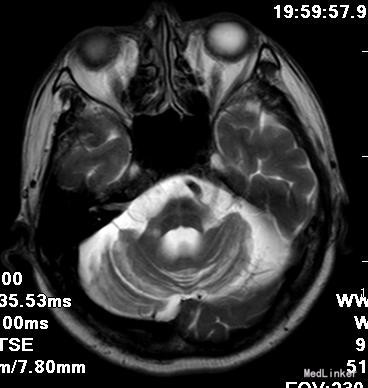

查体:BP:130/80mmHg,神清,言语稍欠清,双瞳孔等大正圆,D=3.0mm,光反射灵敏,双眼球各方向运动不受限,无复视及眼震。双侧鼻唇沟对称,示齿不偏,伸舌居中。张口下颌不偏,悬雍垂居中,双侧咽反射存在,转颈耸肩有力。四肢未见明显肌萎缩,四肢肌力V级,左下肢肌张力稍高。双侧指鼻、轮替、跟膝胫试验均显笨拙。深浅感觉粗查未见明显异常,颈软。Romberg征阴性,蹒氏征阳性,BCR(L++R++),PSR(L++R+++),Babinski'sign(L-R+-),Hoffman(L-,R-)。 辅助检查:头磁共振+MRA:左侧小脑半球脑梗塞可能大,脑萎缩,以小脑及脑干为著。MRA示左侧大脑中动脉远端狭窄。 肌电图:右外展拇短肌,右股四头肌呈神经源性损害,右正中神经运动神经传导速度减慢,双正中神经,左腓浅神经感觉神经传导速度减慢。右尺神经、左面神经重复频率电刺激无明显递减或递增现象。 颈部血管彩超:双侧颈动脉硬化样改变,局部狭窄10%,混合回声斑块,以弱回声为主。

OPCA是一种以小脑性共济失调和脑干损害为主要临床表现的中枢神经系统慢性变性疾病。 临床上,本病于中年或老年前期起病(23~63岁),平均发病年龄(49.22±1.64)岁。男∶女为1∶1。隐袭起病,缓慢进展。可以表现为:1.小脑性共济失调;2.眼球运动障碍;3.自主神经功能障碍;4.锥体束征;5.锥体外系统症状。 彭建平等报道48例OPCA患者MRI表现,其主要征象: (1)脑干形态变细,尤以脑桥前后径变细更为明显,此征象以MR矢状位显示最佳。 (2)小脑体积对称变小,小脑沟裂增宽加深,半球小叶变细变直,呈枯树枝状。此征象在MR轴位或矢状位显示较好。 (3)脑池及脑室扩大,其中以桥前池增宽最明显,小脑及脑干萎缩明显者常有第四脑室扩大。 (4)其他表现:少数可有大脑皮质萎缩。